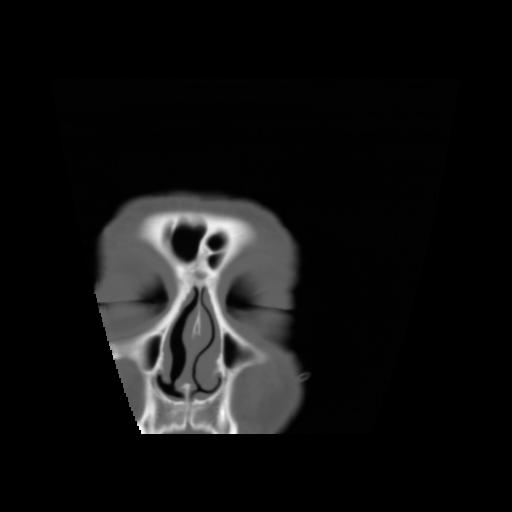

5 CEREBRO,,Coronal,3.000,CEREBRO,Coronal,